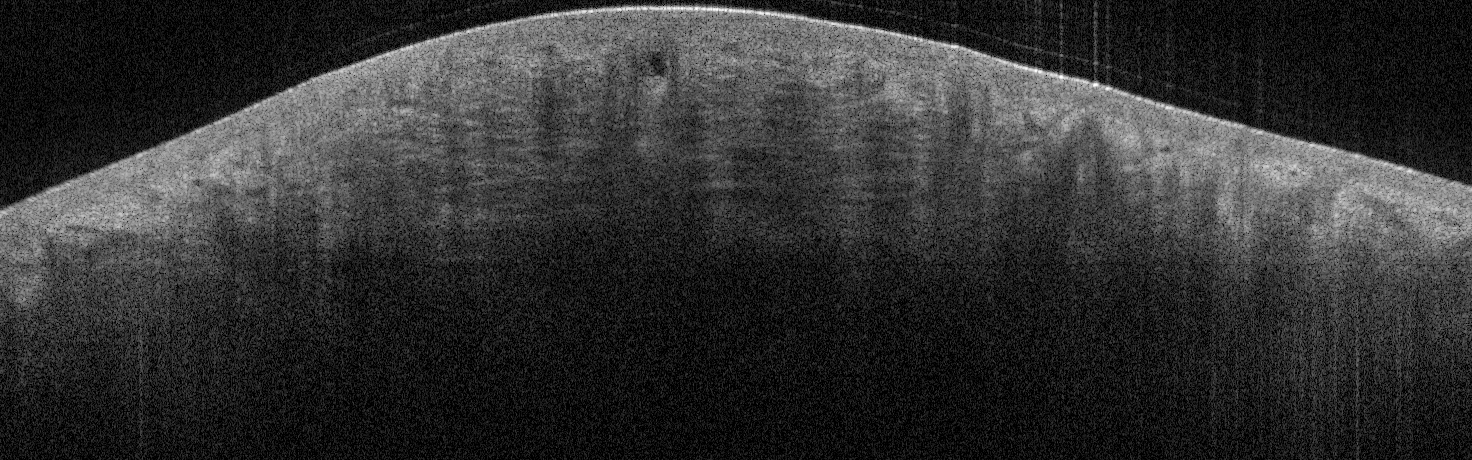

VA43: Right Nasal Ala, Intradermal Melanocytic Nevus

VA43: Right Nasal Ala, Adjacent, Normal